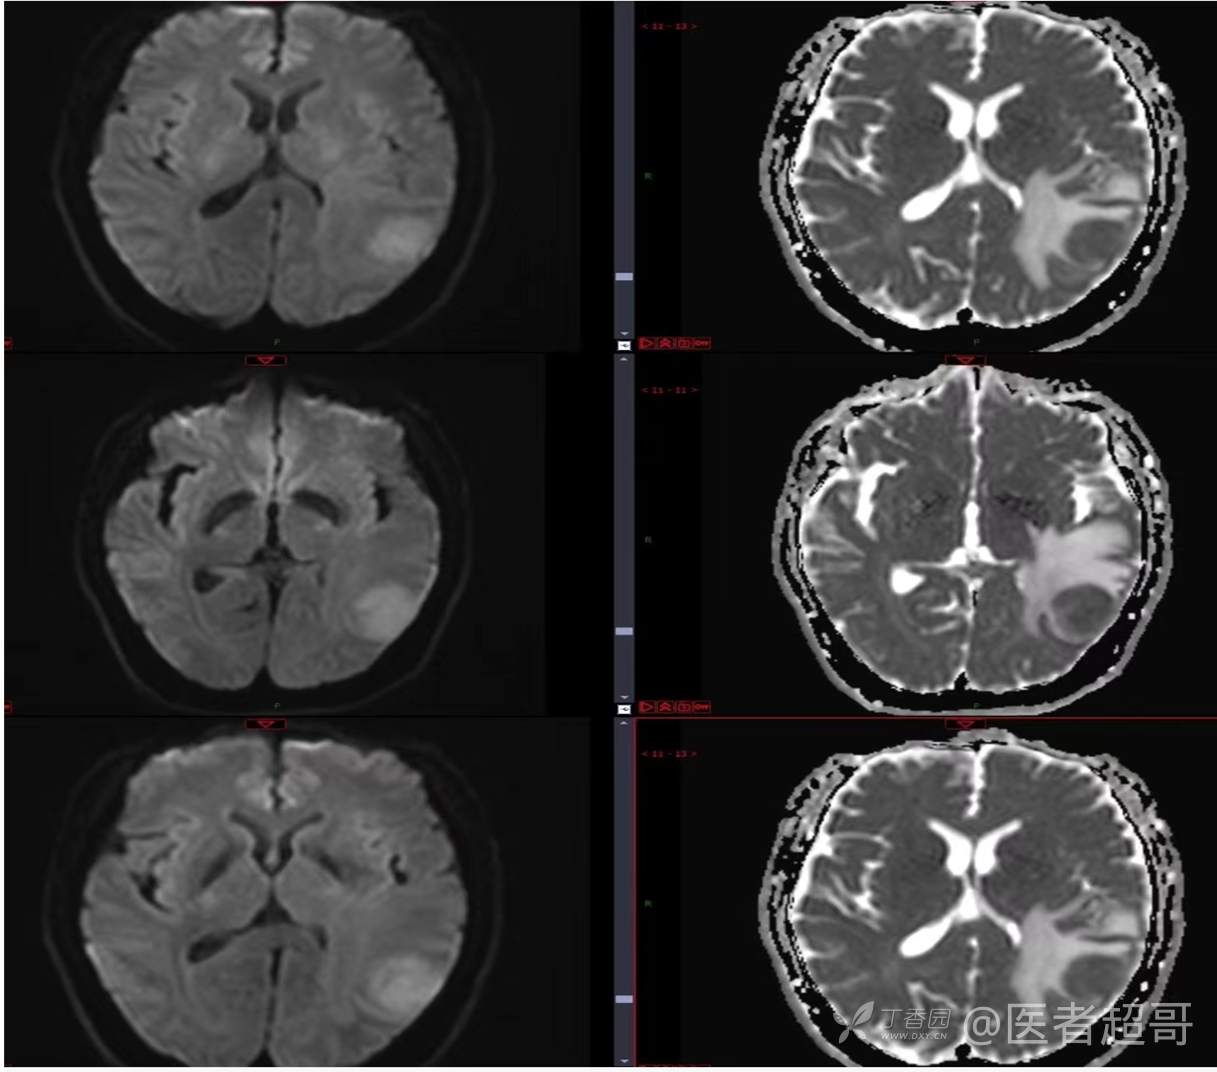

比较典型病例,CT、MRI齐全,请分析,领丁当!

男,56岁

主 诉:查体发现颅内占位10天。

现病史:患者于约10天前于我院查体时行颅脑MRI提示左侧顶叶占位病变,无头痛头晕,无恶心呕杜,无肢体活动不利,无感觉异常,现患者为求进一步治疗,就诊于我科门诊,门诊以“颅内占位性病变”收入我科。患者自发病以来,神志清,精神可,饮食及睡眠差,大小便无明显异常,体重无明显变化。